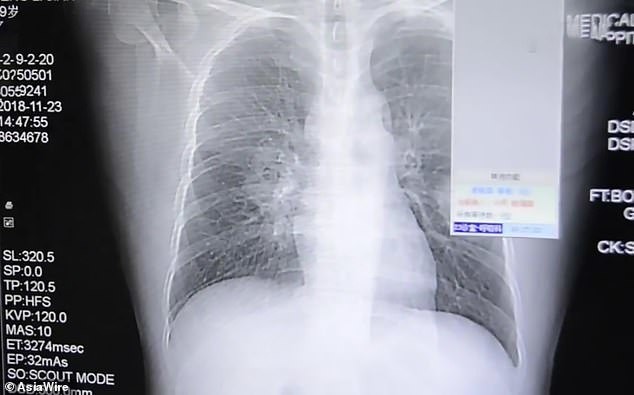

Sau khi tiến hành chụp X-quang, các bác sĩ kết luận người đàn ông này bị nhiễm nấm phổi mức độ nghiêm trọng. Theo một nghiên cứu được công bố trên trang Science Direct, nhiễm nấm phổi là tình trạng sức khỏe nguy hiểm có thể dẫn đến tử vong nếu không phát hiện và điều trị kịp thời.

Kết quả chụp X-quang cho thấy người đàn ông 37 tuổi bị nấm phổi

Điều khiến các bác sĩ băn khoăn là loại nấm mà bệnh nhân hít phải phát triển nhiều trong tất và giày. Khai thác lời kể của bệnh nhân, mọi băn khoăn đã được giải đáp, theo người đàn ông họ Bành, hàng ngày anh thường có thói quen cầm đôi tất đã đi cả ngày của mình và cho lên mũi để ngửi. Từ thông tin trên, các bác sĩ khẳng định rằng sở thích có phần khác người kia chính là nguyên nhân khiến phổi của anh bị nhiễm trùng.